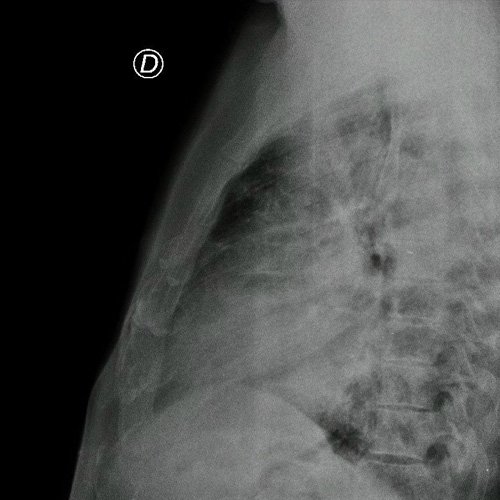

• Radiografía de tórax frente/perfil (Dia 0): rotada, bien inspirada,  índice cardiotorácico impresiona conservado , se observa infiltrado parenquimatoso a nivel medio basal de campo pulmonar derecho e izquierdo,   senos costofrénicos impresionan libres..

Radiografía de tórax frente y perfil